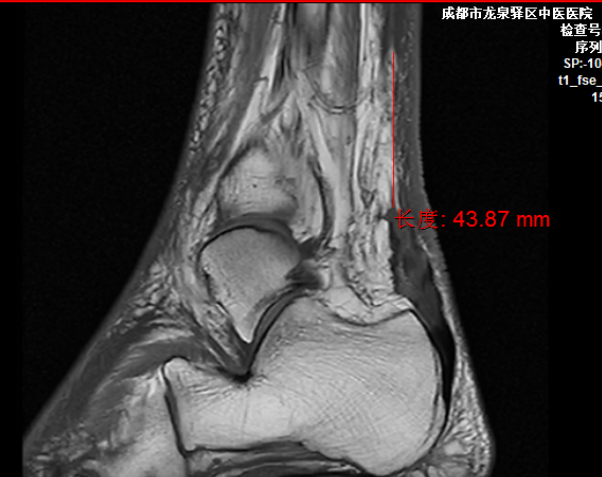

术前MRI示跟腱断裂、缺损

黄某,男,57岁,4月前在家附近不慎扭伤右足踝部,当即感觉右足踝部肿痛、活动受限。患者保守治疗后,足踝部肿痛仍反复发作,遂到我院就诊,经详细查体和完善相关检查后,明确患者为:

1.右侧跟腱断裂(陈旧性);

2.右侧慢性踝关节不稳。